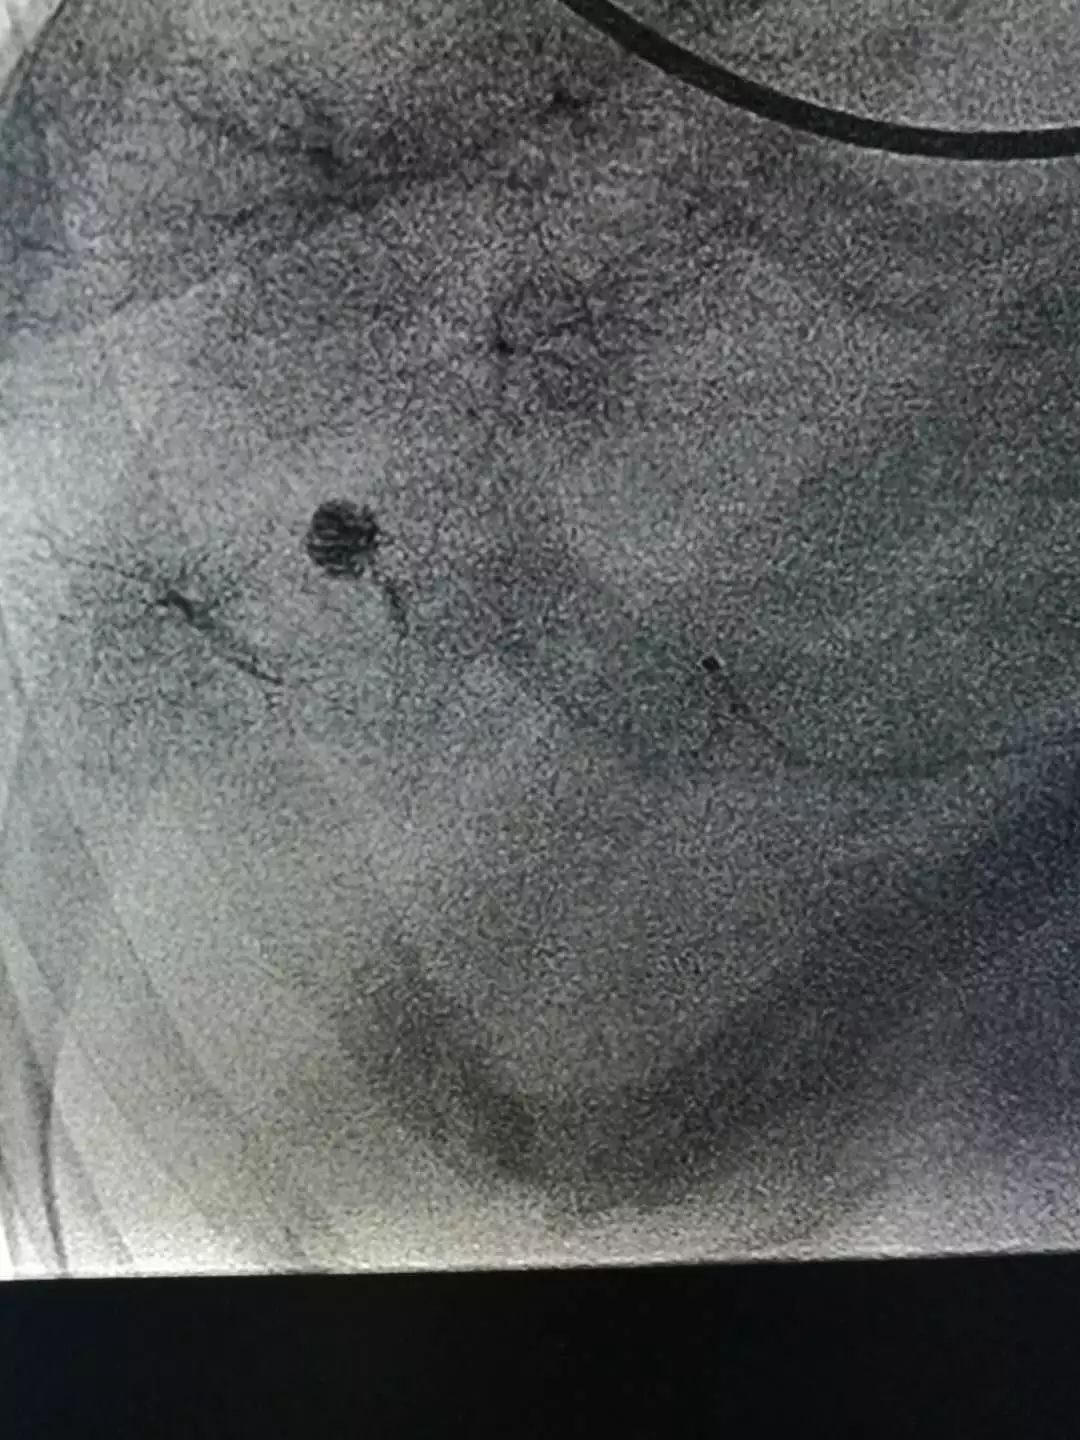

肝血管瘤造影染色

双侧子宫动脉造影,肌瘤以右侧子宫动脉供血为主